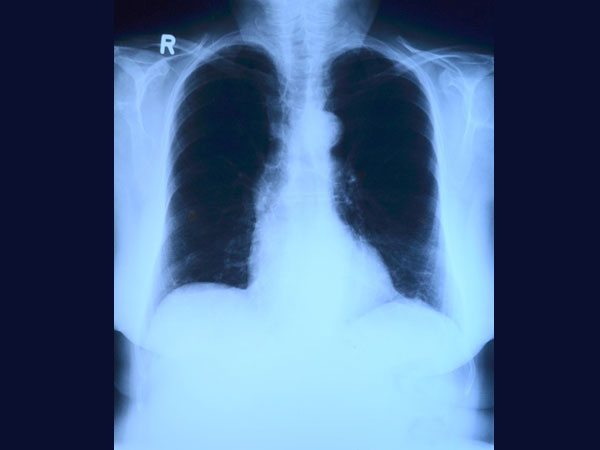

Your doctor would conduct a urine test to determine the presence of Legionella antigens. You could also be prescribed to undergo blood tests, a CT scan in case of neurological symptoms, a chest X-ray to check the infection severity in your lungs and tests on a sample of sputum.

Chest X-rays are usually conducted to see the extent of infection in the lungs.